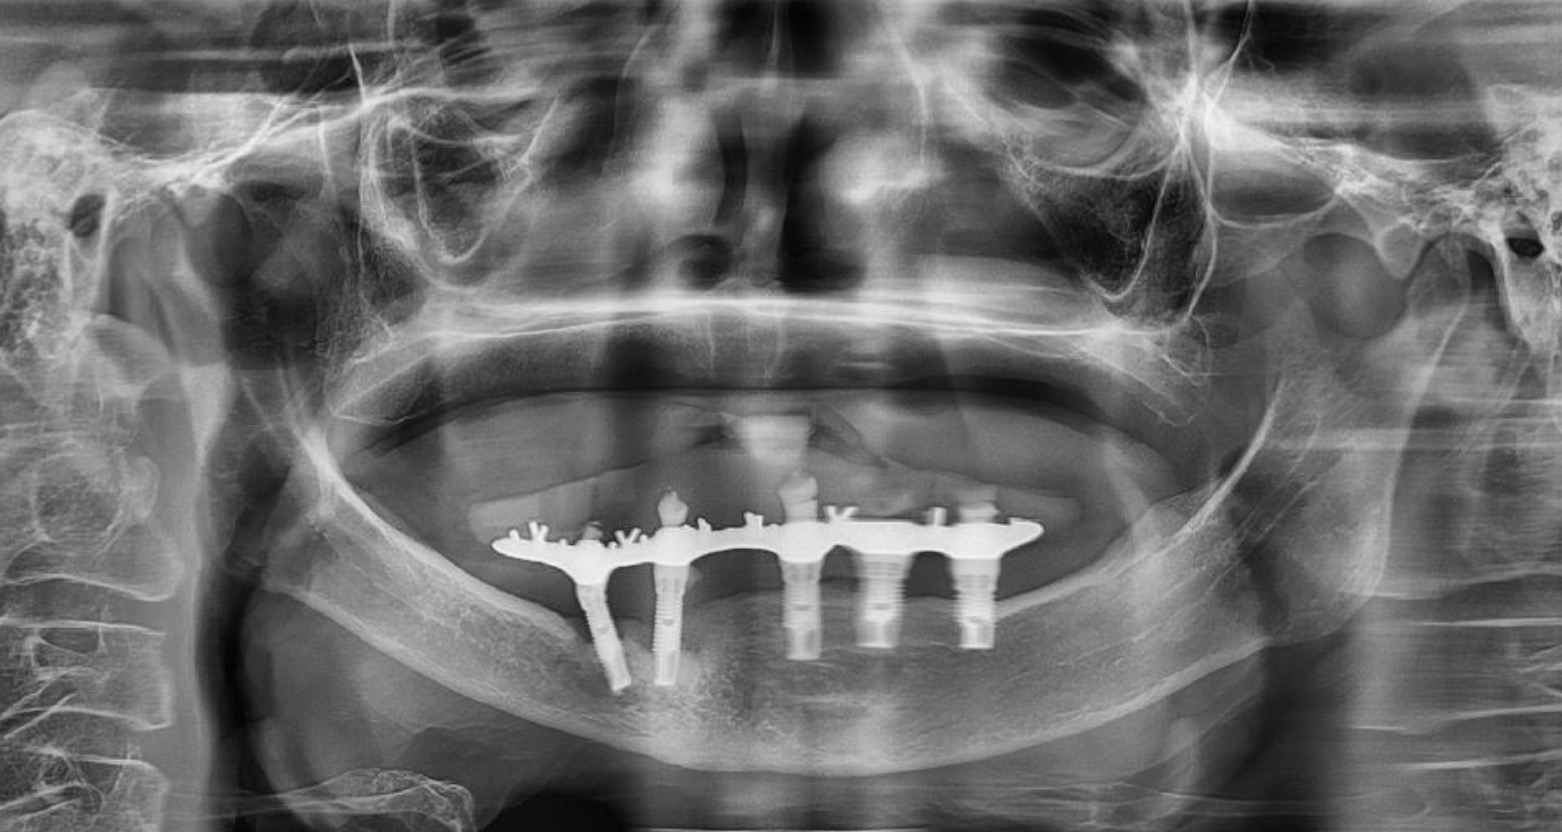

圖2 – 植體周圍堆積厚厚的牙結石,周圍組織已發炎流失

而假牙錯誤不良的咬合設計,導致磨耗不均,假牙螺絲容易鬆脫,影響咀嚼效率,植體周圍炎也已有明顯的破壞程度,植體螺紋已經裸露將近一半,導致All on 4失敗⋯